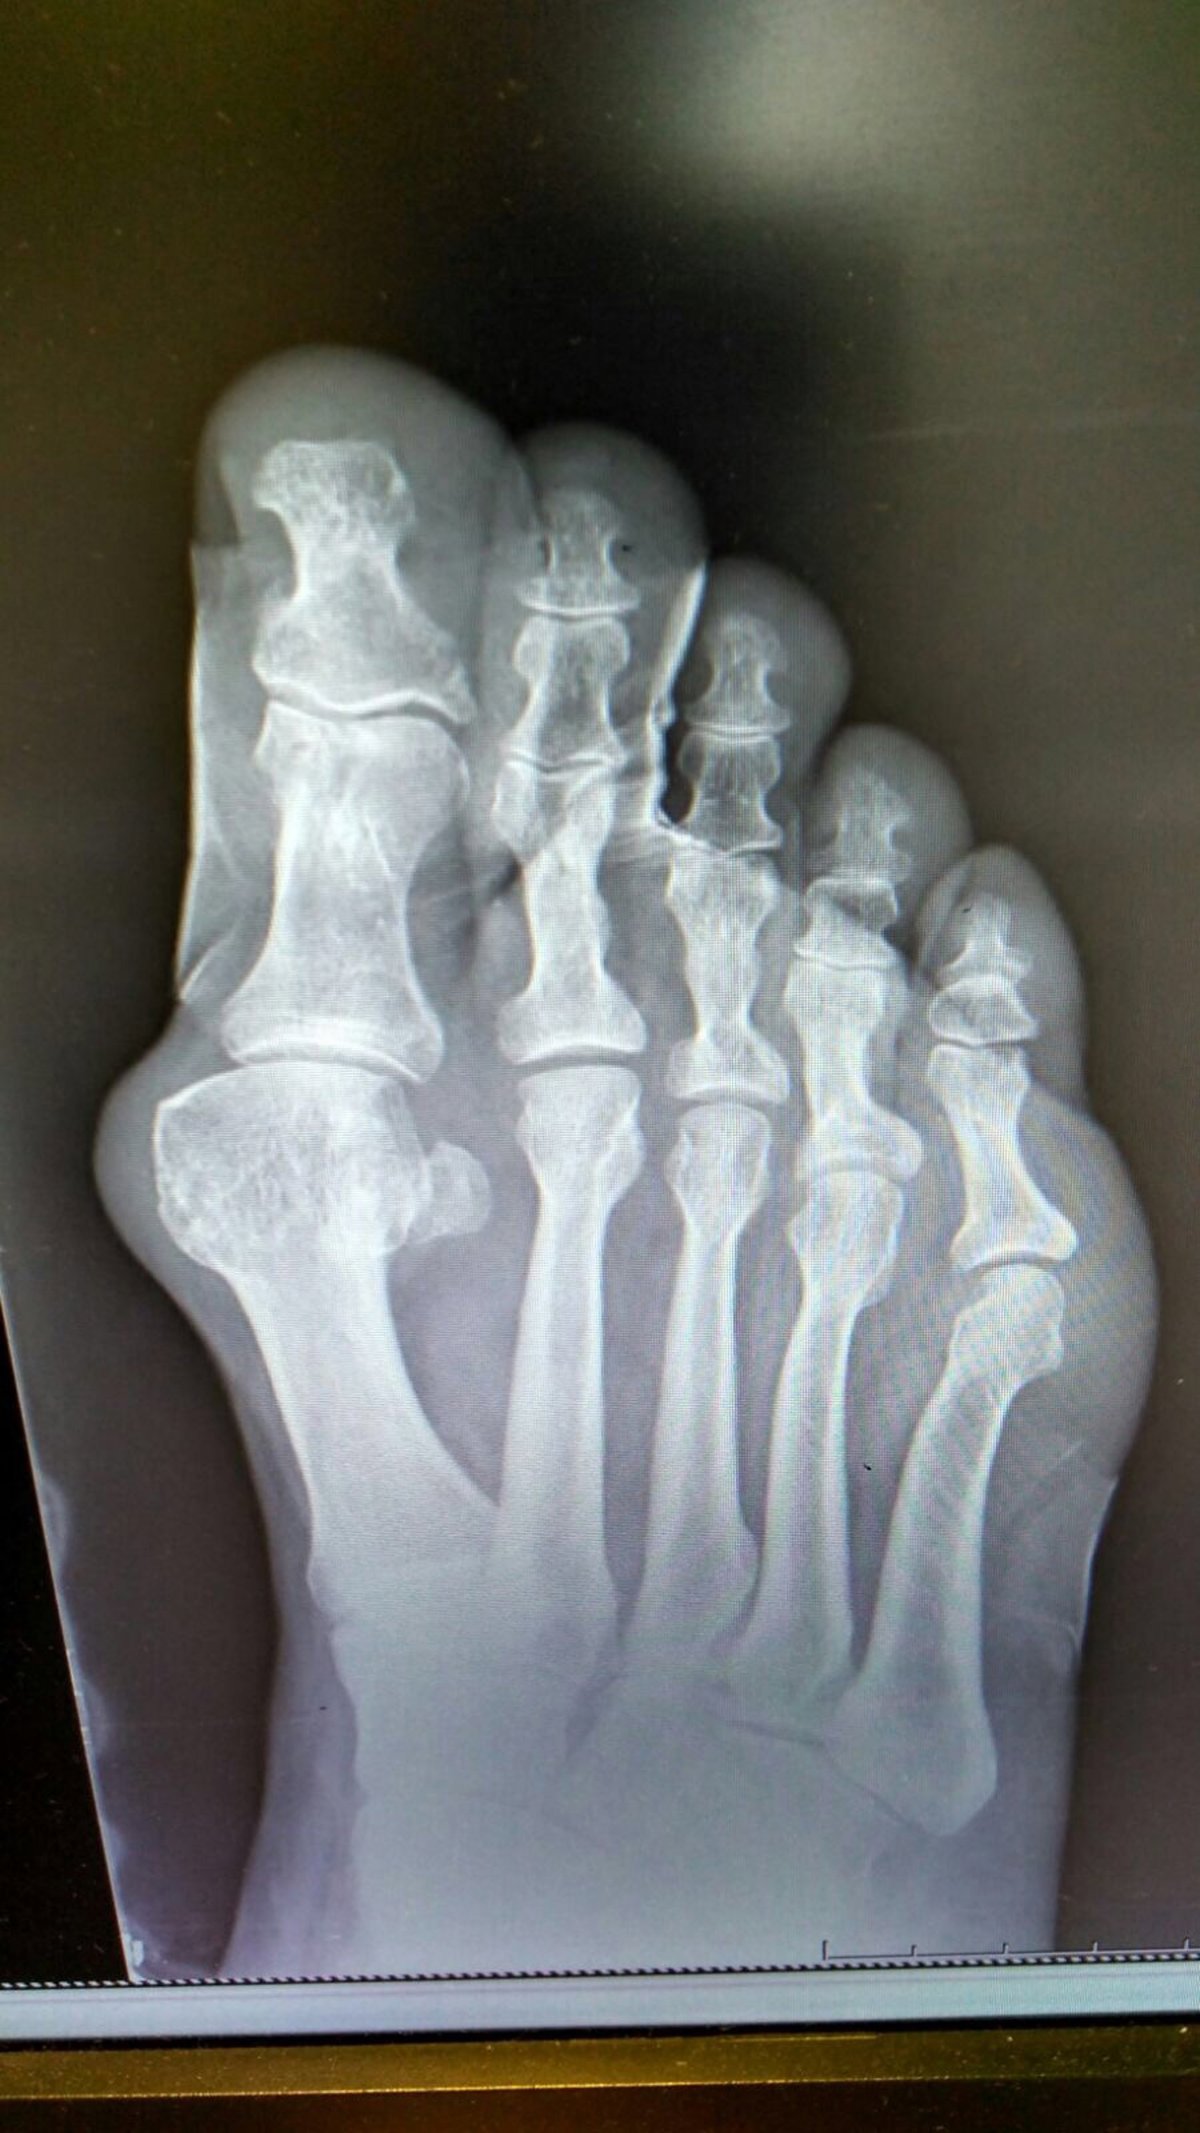

Archivo - Imagen del pie - HOSPITAL LA LUZ - Archivo

Otras afecciones son la atrofia y el desplazamiento de la grasa plantar, que provocará unos puntos de hiperpresión sobre los huesos de la planta de los pies y generará dolor. En este caso, el tratamiento consiste en realizar un estudio biomecánico y confeccionar soportes plantares personalizados diseñados para descargar las zonas de hiperpresión.